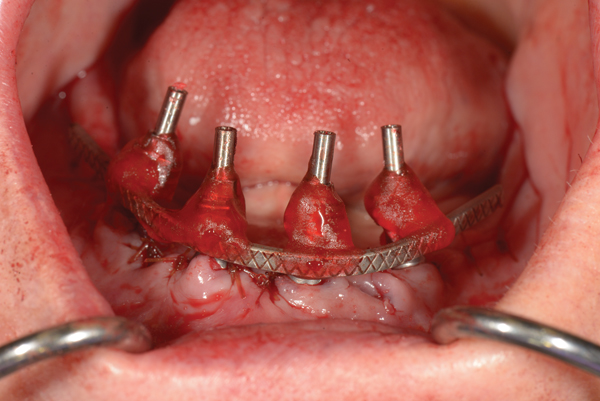

To start, a surgical impression is performed. Open-tray impression copings are secured to the restorative abutments, and a denture-strengthening bar is attached to the copings using a low-expansion pattern resin. The “salt and pepper” technique is used for precise control of the material, thereby avoiding contact with the surgery site and more effectively controlling working time. A plastic impression tray is modified in the occlusal areas where the impression copings will emerge and is tried-in to verify that there are no interferences. Polyvinylsiloxane impression putty is mixed and adapted over the impression copings and denture-strengthening bar. Impression material is also placed in the tray prior to seating. The impression coping screws are exposed and disengaged, allowing the impression to be easily removed. Rigid stabilization of the copings in the impression is verified (Figure 10 through Figure 12). The surgical index is performed using the same provisional prosthesis guide used during the surgery. Only the two anterior implants are indexed. The provisional prosthesis guide is seated to verify the absence of interferences with the two anterior temporary cylinders, and cold-cure acrylic material is applied through the access windows using a “salt and pepper” technique (Figure 13). The prosthesis is held in place with light pressure on the prosthesis guide over the palate or the posterior lingual mandibular ridge until the resin is cured. The VDO is verified after guiding the patient into occlusion with a bite registration recorded in the lab. Esthetic and functional parameters are verified, and the indexed prosthesis is removed with the attached temporary cylinders, and it is then disinfected in cold sterile solution.

Fig 10. Surgical impression—Open-tray impression copings are secured and splinted with a denture-strengthening bar using low-expansion pattern resin.

Figure 10

Fig 11. Surgical impression—Modified plastic impression tray seated to verify that there are no interferences with the copings or the bar.

Figure 11

Fig 12. Surgical impression—After impression putty is adapted around the impression copings and bar, the tray is filled with impression material and seated, the copings are exposed, and the retention screws are disengaged to allow the impression to be easily pulled.

Figure 12